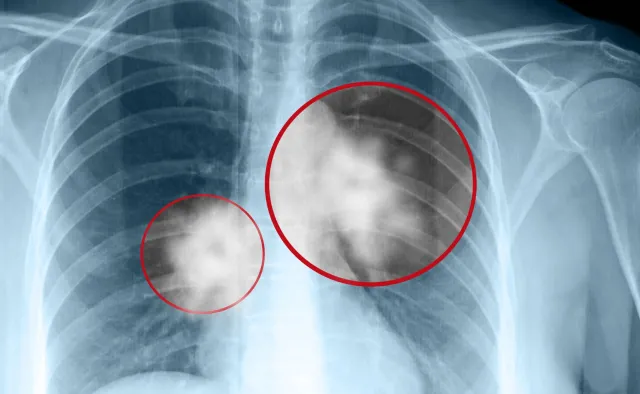

Terapia sekwencyjna polega na wykorzystaniu w kolejnych liniach leczenia metod o innych mechanizmie działania, dzięki którym nawet zaawansowaną chorobę nowotworową z przerzutami u niektórych pacjentów można kontrolować przez wiele lat – wyjaśniała specjalistka.

Taka strategia znacząco poprawiła wyniki leczenia. – W przypadku raka jelita grubego jeszcze w 2000 r. mediana życia chorych z przerzutami wynosiła 12 miesięcy, a teraz mamy ponad 40 miesięcy. To ogromny skok w wynikach leczenia dzięki tym terapiom – powiedziała prof. Wełnicka-Jaśkiewicz.

Jak przypomniał kierownik Kliniki Onkologii i Hematologii CMKP w Szpitalu MSWiA w Warszawie prof. Tadeusz Pieńkowski, zmieniła się definicja nowotworów uznawanych za wyleczalne. – Nie zakłada ona uwolnienia od nowotworu. Za pacjenta wyleczonego z nowotworu uważamy dziś tego, który mimo choroby dożyje wieku odpowiedniego dla danej populacji, i to bez większego uszczerbku w jakości życia – mówił.

Zdaniem specjalisty w tym sensie można mówić, że nowotwory nie są już chorobami nieuleczalnymi, nawet te zaawansowane. – Jest tylko jeden warunek – to, czy możemy pomóc chorym, zależy od tego czym dysponujemy, jakie leki są realnie u nas dostępne. Niestety to, co zostało zarejestrowane na świecie, a czym dysponujemy w naszym (kraju – przyp. red.), to dwie różne sprawy – dodał.

W większości przypadków możemy kontrolować chorobę nowotworową, ale kiedy ta kontrola się kończy - bo nie mamy czym leczyć - to się ona nam wymyka. Jedynie zmiana mechanizmu działania terapii pozwala wyhamować przebieg choroby – wyjaśniała ordynator Oddziału Onkologii Klinicznej z Odcinkiem Dziennym Opolskiego Centrum Onkologii dr Barbara Radecka.